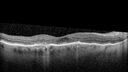

78 year old female No visual complaints referred for evaluation

Medical Hx: Rheumatoid Arthritis. Atrial Fibrillation. Benign Intracranial Hypertension. Sjogrens Syndrome. Osteoporosis.

Systemic Meds: PLAQUENIL (Stopped 2 months ago). Leflunomide. Lidocaine. Gabapentin. Vitamin D. Multaq. DILTIAZEM.

1993 Plaquenil Initially 400 mg /day (9 mg/kg/day x 18 years) then 2011 200 mg daily - (4.6 mg/kg/day x 10 years) STOPPED 3/2021

The patient weighs 100 lbs and is 4’ 2†tall - Images are from 3/2021 and 5/2022

There was no progression 1 year after stopping plaquenil in this patient.